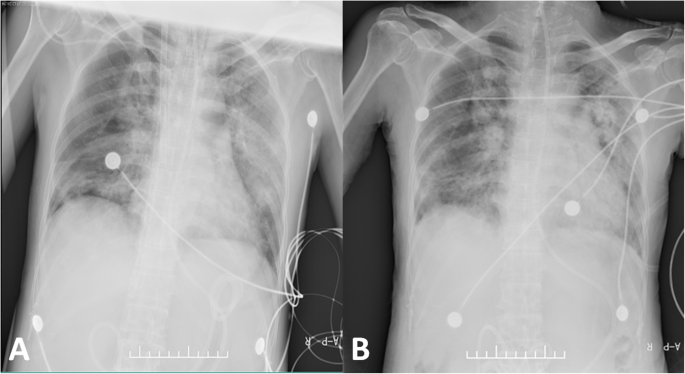

On January 28, 2020, a 49-year-old female patient was transferred to our hospital for further treatment after being diagnosed with COVID-19. At admission, She presented with fever, cough, sputum, and mild dyspnea. Her body temperature was 38 °C, blood oxygen saturation (SPO2) was 93% under ambient air, oxygen inhalation was immediately given by nasal catheter. After admission, levofloxacin and human immunoglobulin were injected into the veins, recombinant with human interferon a2b atomized inhalation. On the 5th day of admission, the disease deteriorated and her mental state was poor, body temperature was 38.8 °C, blood gas analysis: PO2 49 mmHg, PCO2 38 mmHg. She suffered from type I respiratory failure, which conformed to the diagnostic criteria of severe COVID-19 according to the COVID-19 health guidelines of China national health commission. On the 8th day, oxygen inhalation was given by oxygen storage mask (8 L/min), SPO2 was 93%, blood gas analysis: PO2 49 mmHg, PCO2 38 mmHg, Chest CT indicated multifocal ground glass opacities in both lungs with consolidation in partial lungs, which involving more than 75% of the lungs (Fig. 1a). On the 12th day of admission, the patient was anxious, agitated, Alprazolam was administered for sedation. Under high-flow oxygen inhalation (FiO2 90%, 50 L/min), SPO2 was 83 to 90%, blood gas analysis: PO2 55 mmHg, PCO2 44 mmHg, the oxygenation index<70 mmHg, which indicating poor oxygenation status, and non-invasive positive airway pressure ventilation was immediately performed. On the 14th day of admission, SPO2 was 90%, blood gas analysis: PO2 48 mmHg, pCO2 37 mmHg, under the condition of non-invasive positive airway pressure ventilation, FiO2 70%, which revealed poor and difficult to ameliorate hypoxemia, mechanical ventilation became imperative. The patient progressed to critical cases and was transferred to intensive care unit (ICU), mechanical ventilation was performed by orotracheal intubation, ventilator conditions: Volume Control ventilation, VT 240 ml, VF 15 times/min, FiO2 100%, PEEP 10 cm H2O, prone position ventilation was performed at the same time. After intubation, maintaining the use of propofol and midazolam for sedation, SPO2 rose to 95% and hypoxemia improved. On the 16th day of admission, the patient’s SPO2 was difficult to maintain with poor oxygenation index and high airway platform pressure, salvage VV-ECMO therapy was performed. Under the guidance of B-ultrasound, the right femoral vein was inserted into the inflow cannula, the right jugular vein was inserted into the outflow cannula, the venous cannula was 20F, the arterial cannula was 17F, the depth of venous cannula was 43 cm, and the depth of arterial cannula was 14 cm. Initial ECMO parameters: speed 3200 rpm, flow 5 L/min, Sweep gas 3 L/min, FiO2 70%. Coordinated ventilator parameters: Assist-Control ventilation, VT 210 ml, VF 18 times/min, FiO2 40%, PEEP 12 cm H2O. Reviewed blood gas analysis: PO2 84 mmHg, PCO2 46 mmHg, oxygenation index improved significantly after ECMO. During the treatment of ECMO, deep sedation was performed and heparin was continuously pumped to maintain activated partial thromboplastin time (APTT) being 40–60s. On the 19th day of admission, support condition of ECMO for the patient was still high, ECMO could not be removed in a short time, and the lung compliance was poor. Chest radiograph showed increased multiple patchy density shadows in both lungs (Fig. 2a). We decided to coordinating prone position ventilation to improve pulmonary ventilation-to-perfusion ratio. On the 22th day of admission, bronchoscopy showed: a little white sputum could be seen in the main bronchus, and slightly swelling, hyperemia could be seen in the grade 1–4 bronchial mucosa of both lungs. On the 27th day of admission, the patient was tested negative for SARS-CoV-2 nucleic acid by the fluorescence quantitative RT-PCR for two consecutive times. After the withdrawal of sedative drugs, the patient was conscious, had a firm handshake, we stopped the ventilator, ECMO parameters was adjusted: speed 3600 rpm, flow 4 L/min, Sweep gas 3 L/min, FiO2 70%, oxygen was inhaled through the endotracheal tube whit high-flow oxygen therapy (FiO2 45%, 40 L/min). After observated for 30 min, blood gas analysis: PO2 71 mmHg, pCO2 45 mmHg, heart rate was 83 beats per minute, breathing rate was 25 times per minute, and blood pressure was 136/63 mmHg, the endotracheal tube was removed, awake ECMO was performed. Treatment strategies during awake ECMO stage: 1. Strengthen the monitoring and management of bleeding and thrombosis, monitoring the levels of hemoglobin, platelets, APTT and fibrinogen, and set the corresponding target values to be 90 g/L, 100*10^9/L, 40S, 2.0 g/L respectively, supplement the substrate by transfuse some components of blood if failed to meet target values. 2. Pulmonary rehabilitation: prone position or high lateral lying position was adopted for drainage to promote lung recruitment, and a large dose of ambroxol and acetylcysteine were used to dispersing phlegm. 3. During the awake ECMO period, patients had intermittent anxiety and delirium, enhanced psychological counseling, quetiapine and haloperidol were given to fight anxiety and delirium. 4. Combined Piperacillin tazobactam, Datomycin and Voriconazole to fight infection. 5. Strengthen liquid management and nutritional support therapy. On the 35th day of admission, the patient’s oxygen saturation could be maintained at 98%. After re-examination of chest radiograph (Fig. 2b), the patient was evacuated from ECMO. Reexamination chest CT on March 6, 2020 indicated the ground glass opacities absorbed, and leave some fibrotic stripes (Fig. 1b). After further treatments of anti-infection, pulmonary rehabilitation, nutritional support, psychological counseling and physical rehabilitation, the patient recovered and was discharged on March 15, 2020.